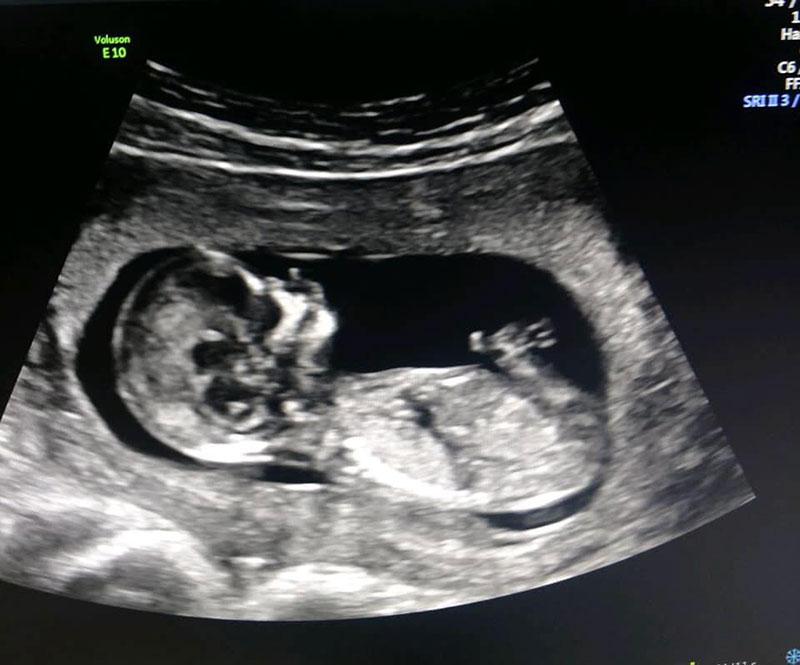

การเตรียมพร้อมที่จะมีลูกครั้งนี้ไม่ได้เกิดขึ้นแบบปุบปับ ครอบครัวทั้งสองฝ่ายต่างวางแผนเตรียมความพร้อมกันมานานร่วมสองปี โดยเมื่อถึงเวลาที่เหมาะสม พวกเขาได้ทำเด็กหลอดแก้วหรือไอวีเอฟ (IVF - In-vitro Fertilization) ซึ่งเป็นการปฏิสนธินอกร่างกาย ไข่ของเลอาถูกนำมาผสมกับน้ำเชื้อของแมทธิวเพื่อฟักเป็นตัวอ่อน และนำไปฝังในมดลูกของเซซิล สิ่งที่น่าทึ่งก็คือ ทุกอย่างผ่านพ้นไปได้ด้วยดีตั้งแต่การลองครั้งแรก เรียกได้ว่าดีเกินกว่าที่ทุกคนคาดหมาย